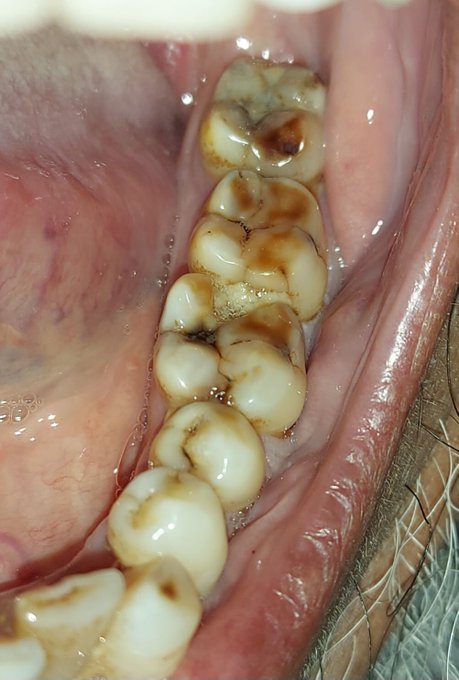

Clinical examination showed caries involving the distal surface of tooth no.36 along with food impaction. Diagnosis irreversible pulpitis in tooth no.36

Diagnosing irreversible pulpitis typically involves a thorough examination by a dentist. Clinical evaluation, alongside a patient’s description of symptoms, plays a vital role in diagnosis. X-rays are also essential, as they can reveal the extent of damage and whether the condition has progressed to affect the root. The dentist may also perform pulp testing to determine the vitality of the affected tooth’s pulp.